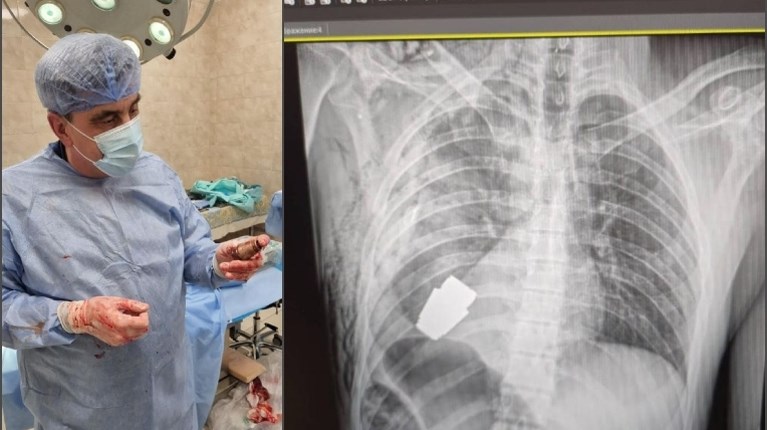

Οι χειρούργοι αφαίρεσαν τη χειροβομβίδα που βρισκόταν ακριβώς κάτω από την καρδιά του τραυματισμένου στρατιώτη. Καθόλη τη διάρκεια της επέμβασης, δύο σκαπανείς του ουκρανικού στρατού επέβλεπαν την διαδικασία, όπως δήλωσε η Χάνα Μάλιαρ, αναπληρώτρια υπουργός Άμυνας της Ουκρανίας. Η Ουκρανή αξιωματούχος έκανε αναρτήσεις σε λογαριασμό της στα κοινωνικά δίκτυα με τη φωτογραφία του γιατρού που αφαίρεσε με επιτυχία τη χειροβομβίδα, να την κρατά στο χέρι του αμέσως μετά το χειρουργείο.

Στην ακτινογραφία φαίνεται η χειροβομβίδα τύπου VOG μέσα στο σώμα του στρατιώτη του πυροβολικού.

Η επέμβαση διεξήχθη χωρίς τη χρήση ηλεκτροπηξίας, μια ιατρική τεχνική μέθοδο για τον έλεγχο της αιμορραγίας κατά τη διάρκεια της επέμβασης, επειδή "η χειροβομβίδα μπορούσε να εκραγεί ανά πάσα στιγμή".